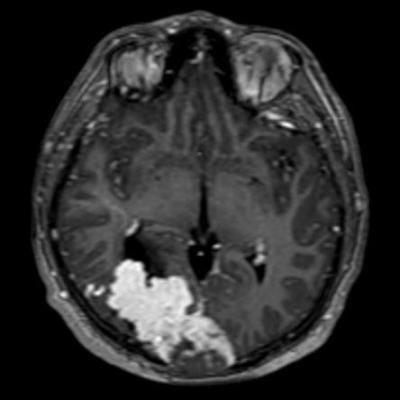

44 yaş, E

Baş ağrısı

hemorajik glioblastoma multiforme (GBM, WHO Grade 4)